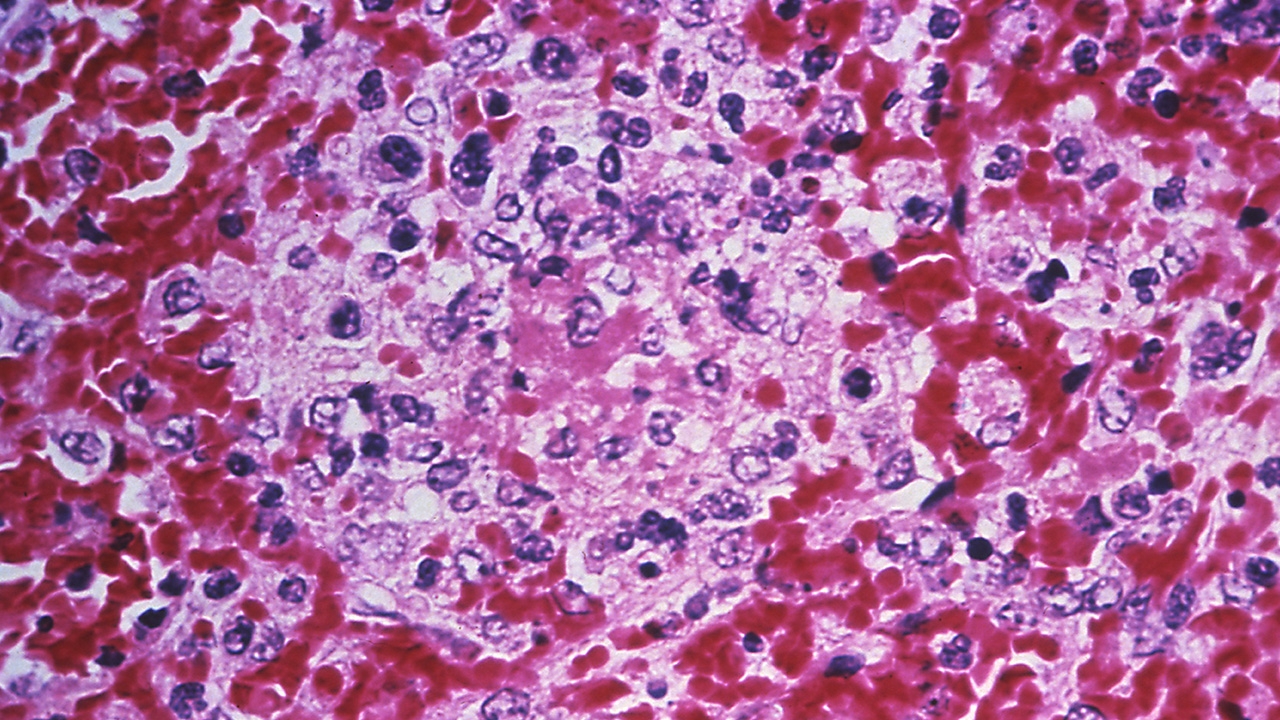

กาฬโรคต่อมน้ำเหลืองมีสาเหตุจากการติดเชื้อแบคทีเรียที่เรียกว่า Yersinia pestis ซึ่งแฝงตัวอยู่ในสัตว์ฟันแทะในภูมิภาคเอเชียกลางมายาวนานหลายศตวรรษ กระทั่ง ณ จุดหนึ่งในช่วงต้นทศวรรษที่ 1300 มันก็กลายพันธุ์กลายเป็นเชื้อมรณะที่มีโอกาสติดต่อสู่คนสูงมาก

คำว่าแบล็กเดธ เริ่มถูกใช้อย่างแพร่หลายเพื่อเรียกการระบาดครั้งนี้ในช่วงทศวรรษที่ 1750 สื่อถึงอาการขั้นสุดท้ายของผู้ป่วยที่ร่างกายจะกลายเป็นสีดำเพราะมีเลือดออกใต้ผิวหนังชั้นหนังกำพร้า และยังมีความนัยสื่อถึง ความน่าสะพรึงกลับของโรคมรณะชนิดนี้ด้วย